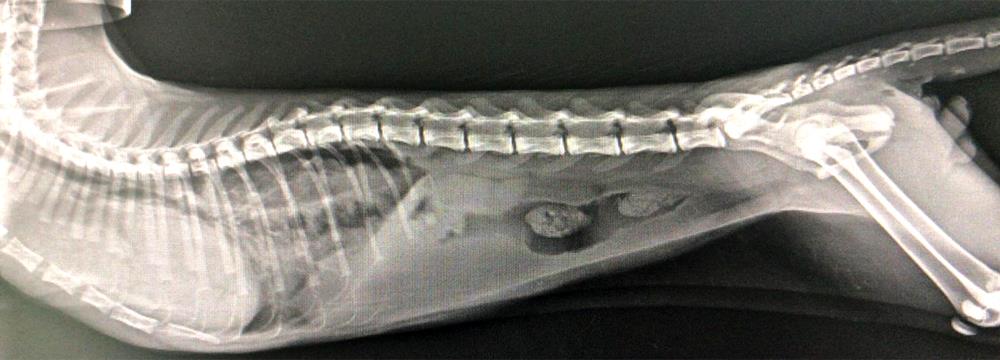

3 Aylik Kedide Diyafram Fitki Diaphragmatic Hernia Beyaz Pati Veteriner Klinigi